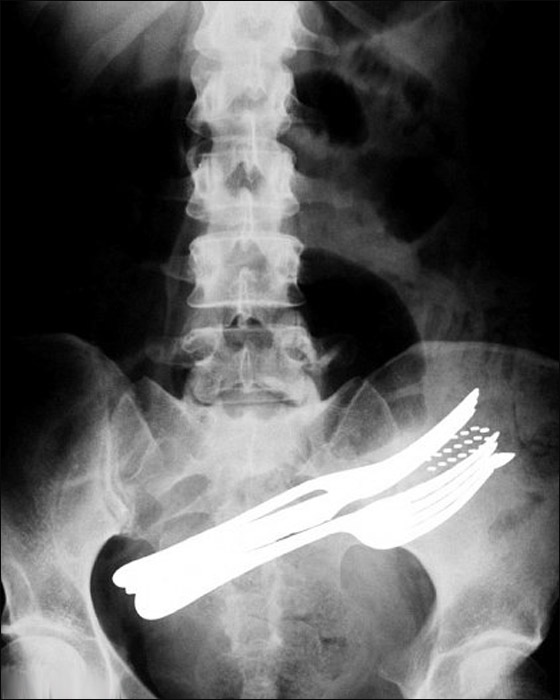

أدوات طعام في جوف مريض!! |

ورغم أن الصور ممعنة في الغرابة ومذهلة للغاية إلا أنها تأتي بلا تفسير، وتشمل مريضا ابتلع شوكتي طعام وفرشاة أسنان وقلم حبر جاف. ومن حسن الحظ أن الجراح استطاع بمشرطه استخراج أدوات الطعام هذه من جوف المريض. وتوضح صورة أخرى رجلا ابتلع مفتاحا ولكنه لم يتخلص منه إلا بعملية جراحية.

أدوات طعام في جوف مريض